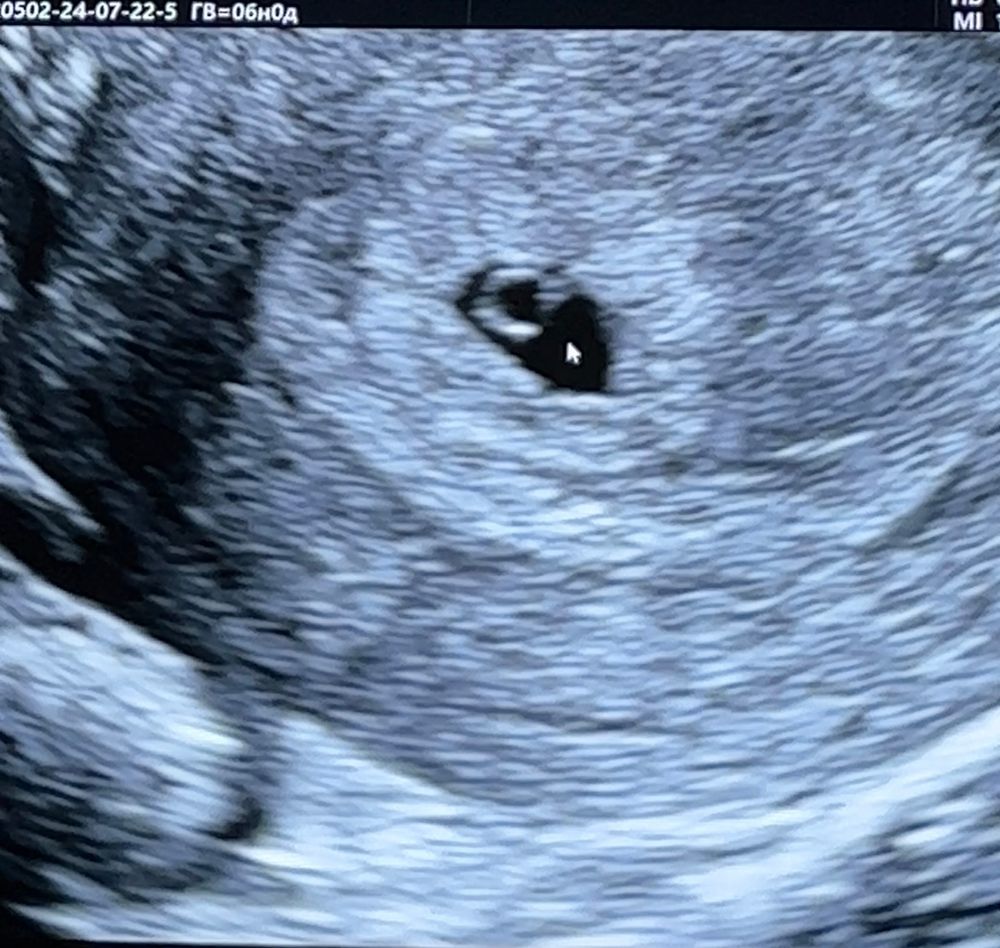

недели не эмбриона

4 5 недели не эмбриона 146 фото